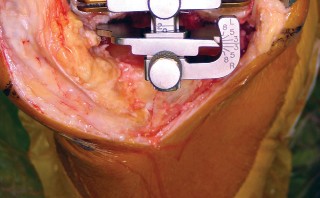

يركز هذا النهج على استخدام فتحة المفصل شبه الرضفية الإنسية المحدودة (Limited Medial Parapatellar Arthrotomy) وشق العضلة الرباعية المحدود، وهو جزء من مجموعة من الأساليب المعدلة التي توفر وصولاً ورؤية محدودين، ولكن يمكن تحويلها إلى نهج تقليدي إذا لزم الأمر. هذا يعني أن الجراح يمكنه البدء بتقنية أقل توغلاً، مع الاحتفاظ بالقدرة على التكيف إذا كانت الحالة تتطلب رؤية أوسع.

يُعد النهج شبه الرضفي الإنسي المحدود في جراحة استبدال مفصل الركبة الكلي بالحد الأدنى من التدخل الجراحي خيارًا مألوفًا ومتعدد الاستخدامات، وقد تطور مع إضافة أدوات أصغر وأكثر كفاءة. يتميز هذا النهج بقدرته على التكيف مع مجال العمليات المحدود في الركبة، مما يسمح بتشريح جراحي محدود دون المساس بالإجراء أو النتائج.

كيف يؤثر التدخل الجراحي المحدود على الأنسجة

في جراحة استبدال مفصل الركبة التقليدية، يتم إجراء شق كبير لتمكين الجراح من الوصول الكامل إلى المفصل ورؤية جميع الهياكل. هذا قد يتطلب قطعًا أوسع في العضلات والأوتار والأنسجة الرخوة المحيطة. في المقابل، يهدف النهج شبه الرضفي الإنسي المحدود إلى: